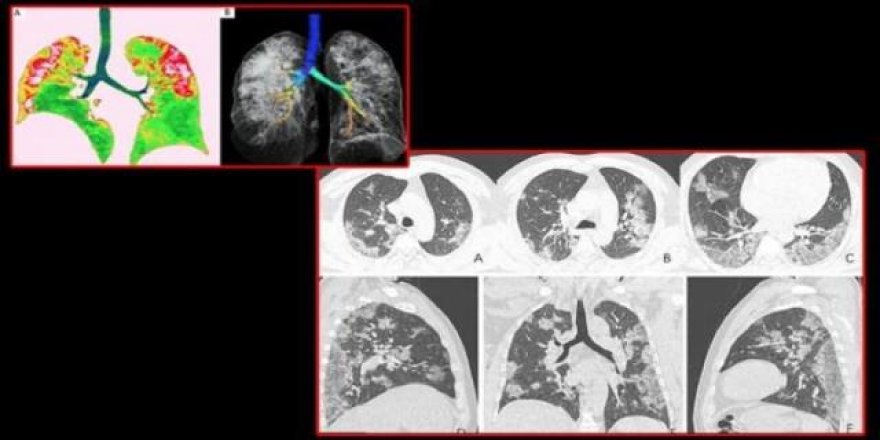

İlk korona virüs vakasına hibrit tedavi